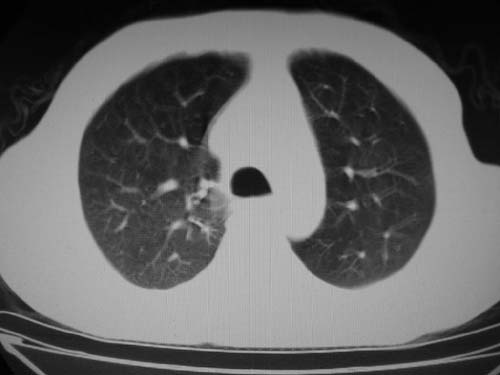

男,80岁

肺动脉段突出,左右肺门不等大,左肺门明显增大,肺动脉干及左肺动脉明显增宽,考虑先天性肺动脉狭窄瓣膜狭窄型。

肺动脉高压,左肺动脉瘤样扩张。